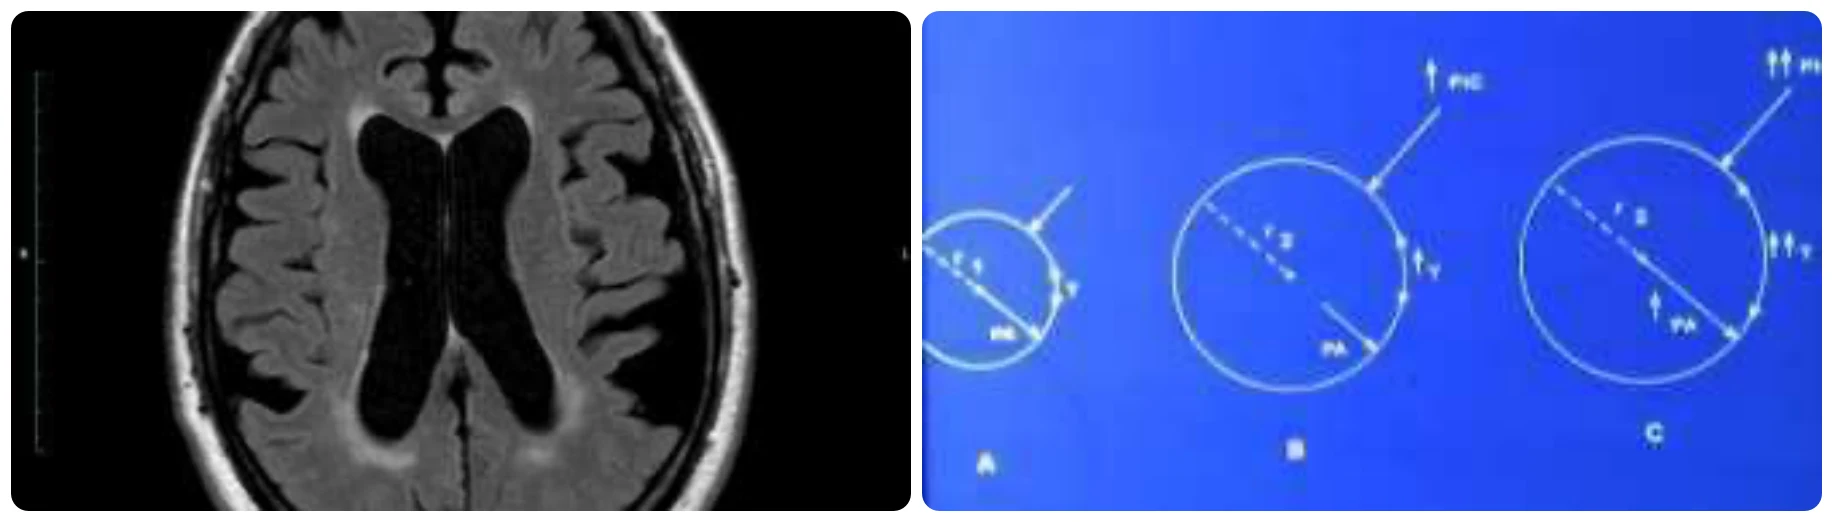

Hallazgos en Resonancia Magnética – Índice de Evans y Ángulo Calloso

La resonancia es realmente una herramienta muy precisa para hacer el diagnóstico:

Edema transependimario: Primero porque se ve el edema transependimario, que se ve como esta zona blanca alrededor de los ventrículos.

Ángulo calloso: Después porque hay unos ángulos que se pueden medir. Este ángulo que es agudo, menor de 90º, es porque el globo ventricular, como esta estructura del cuerpo calloso es muy fija, lo que va a hacer el aumento de presión de los ventrículos es cerrarlo sobre esa estructura.

Índice de Evans: Y después también hay un índice que es la relación entre toda la corteza cerebral de esta longitud y la longitud del ventrículo.